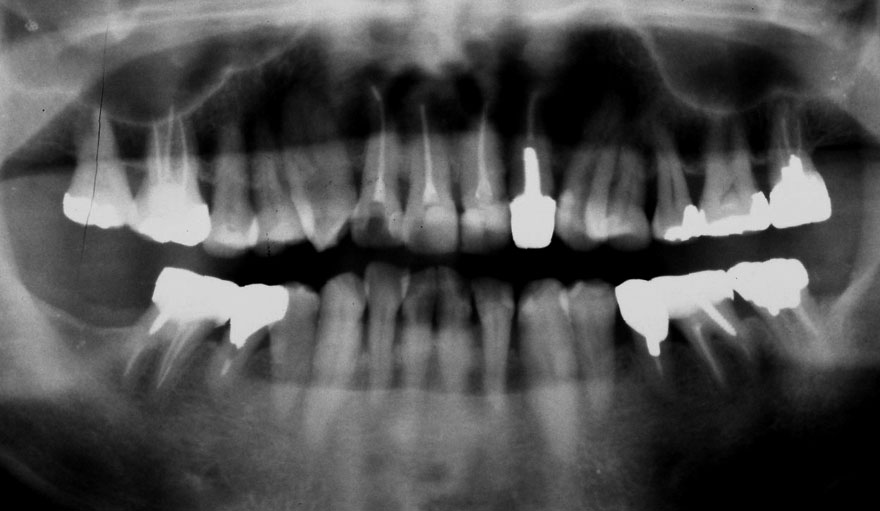

初診時 38歳 男性 平均歯槽骨喪失量:6.520mm

25年後 63歳

平均歯槽骨喪失量:8.57mm

25年間喪失量:-2.05mm

年間喪失速度:-0.08mm

(ケア頻度:1.38ヵ月ごと)